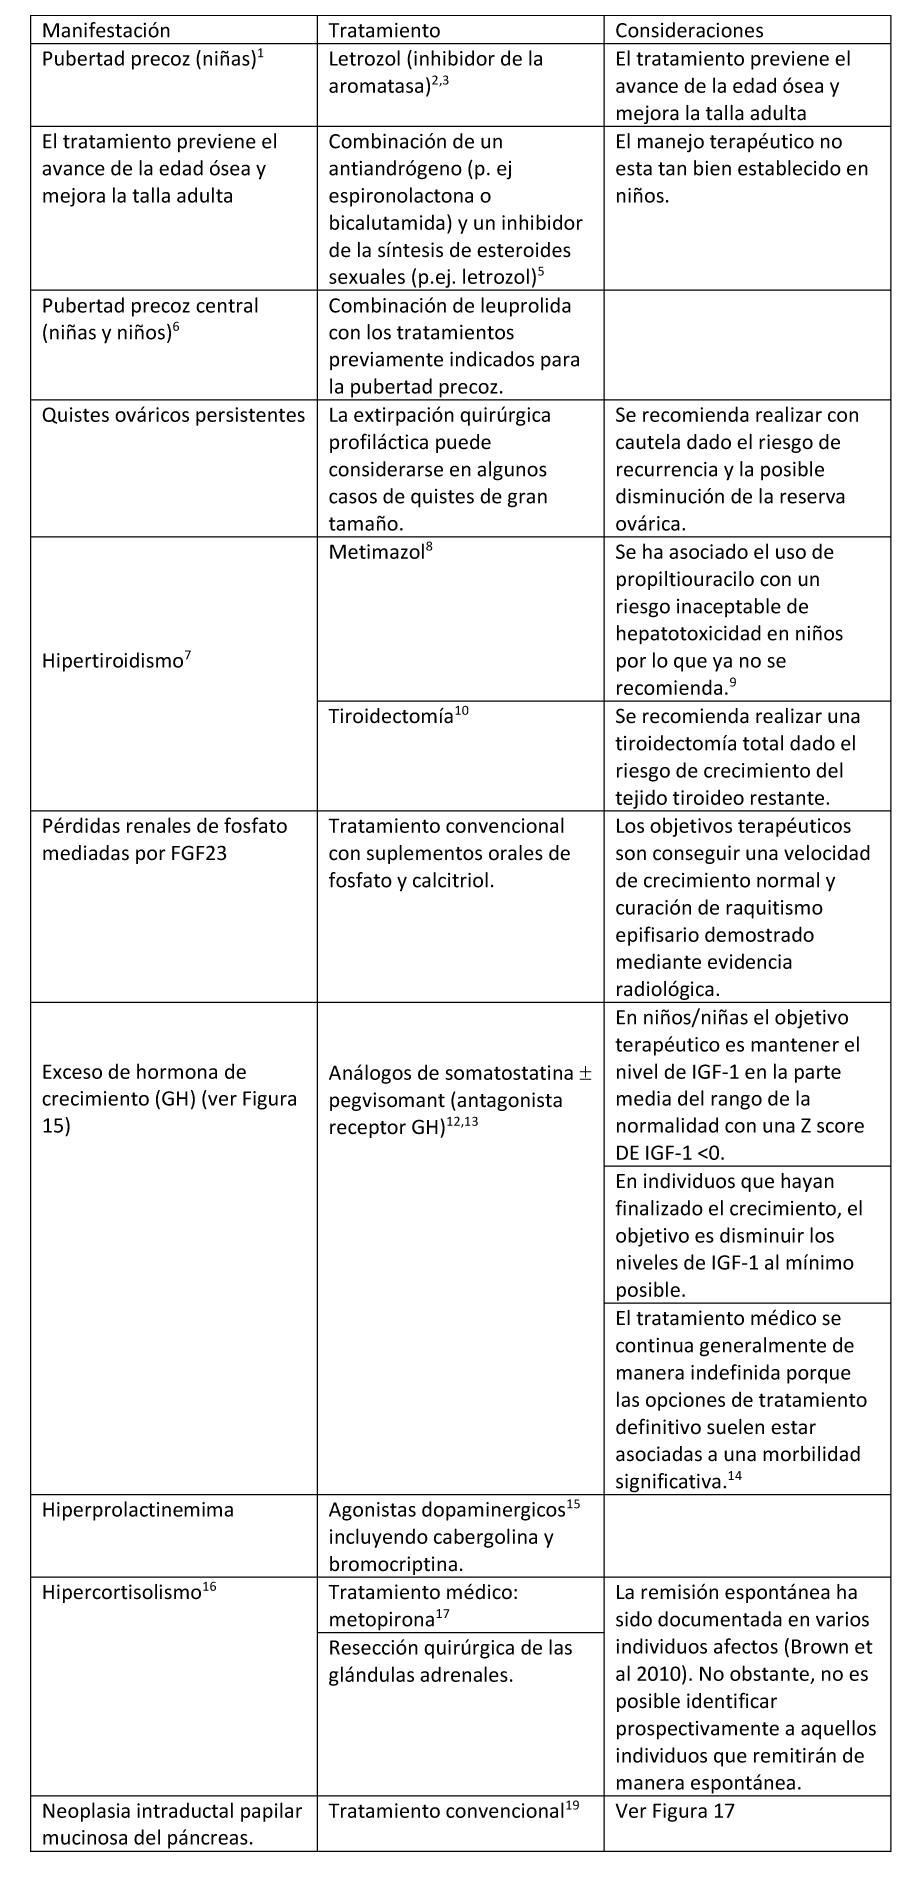

Tabla 4. Tratamiento de Endocrinopatías en individuos con Displasia Fibrosa/Síndrome de McCune-Albight

- Ver Figura 12. La mayoría de las niñas tendrán una disminución en el número de sangrados menstruales durante el tratamiento.

- Feuillan et al (2007)

- El tratamiento con letrozol produjo efectos beneficiosos prolongados sobre la maduración esquelética, velocidad de crecimiento, y talla final adulta (Estrada et al 2016).

- Ver Figura 13. La pubertad precoz no es frecuente en varones.

- Boyce et al 2012a.

- Dada la exposición prematura a esteroides sexuales (ver Descripción Clínica), la pubertad precoz central puede presentarse a pesar de que el/la niño/a tuvieran un buen control de la pubertad precoz periférica.

Figura 12. Manejo clínico recomendado para la pubertad precoz en niñas con Displasia Fibrosa/Síndrome de McCune-Albright